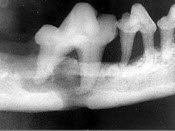

69、单项选择题

发现下前牙变色,唇侧牙龈一肿物一月余,经X线检查,结果如图

。最可能的诊断是()

A.根尖囊肿

B.牙龈瘤

C.根尖脓肿

D.成釉细胞瘤

E.牙骨质瘤